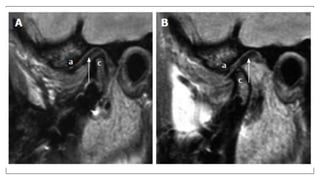

• To evaluate the position and integrity of disk inTMJ.

Normal anatomy

Pathologies